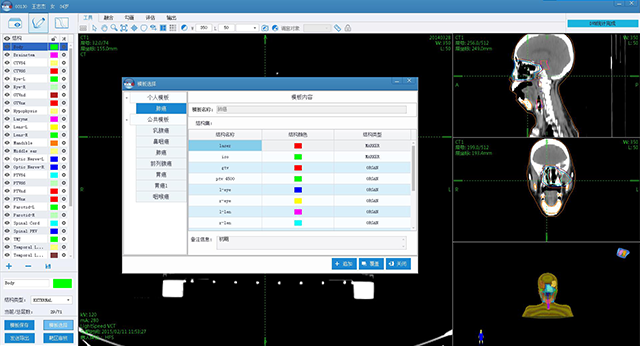

è‚؟çک¤و”¾ç–—ن؟،وپ¯هŒ–ن؛§ه“پ

ه®‰è¯؛ن؛‘و™؛è؟œç¨‹و”¾ç–—هچڈن½œه¹³هڈ°

ن؛§ه“پن¸ژو•ˆهٹ³

ن؛§ه“پن¸ژو•ˆهٹ³